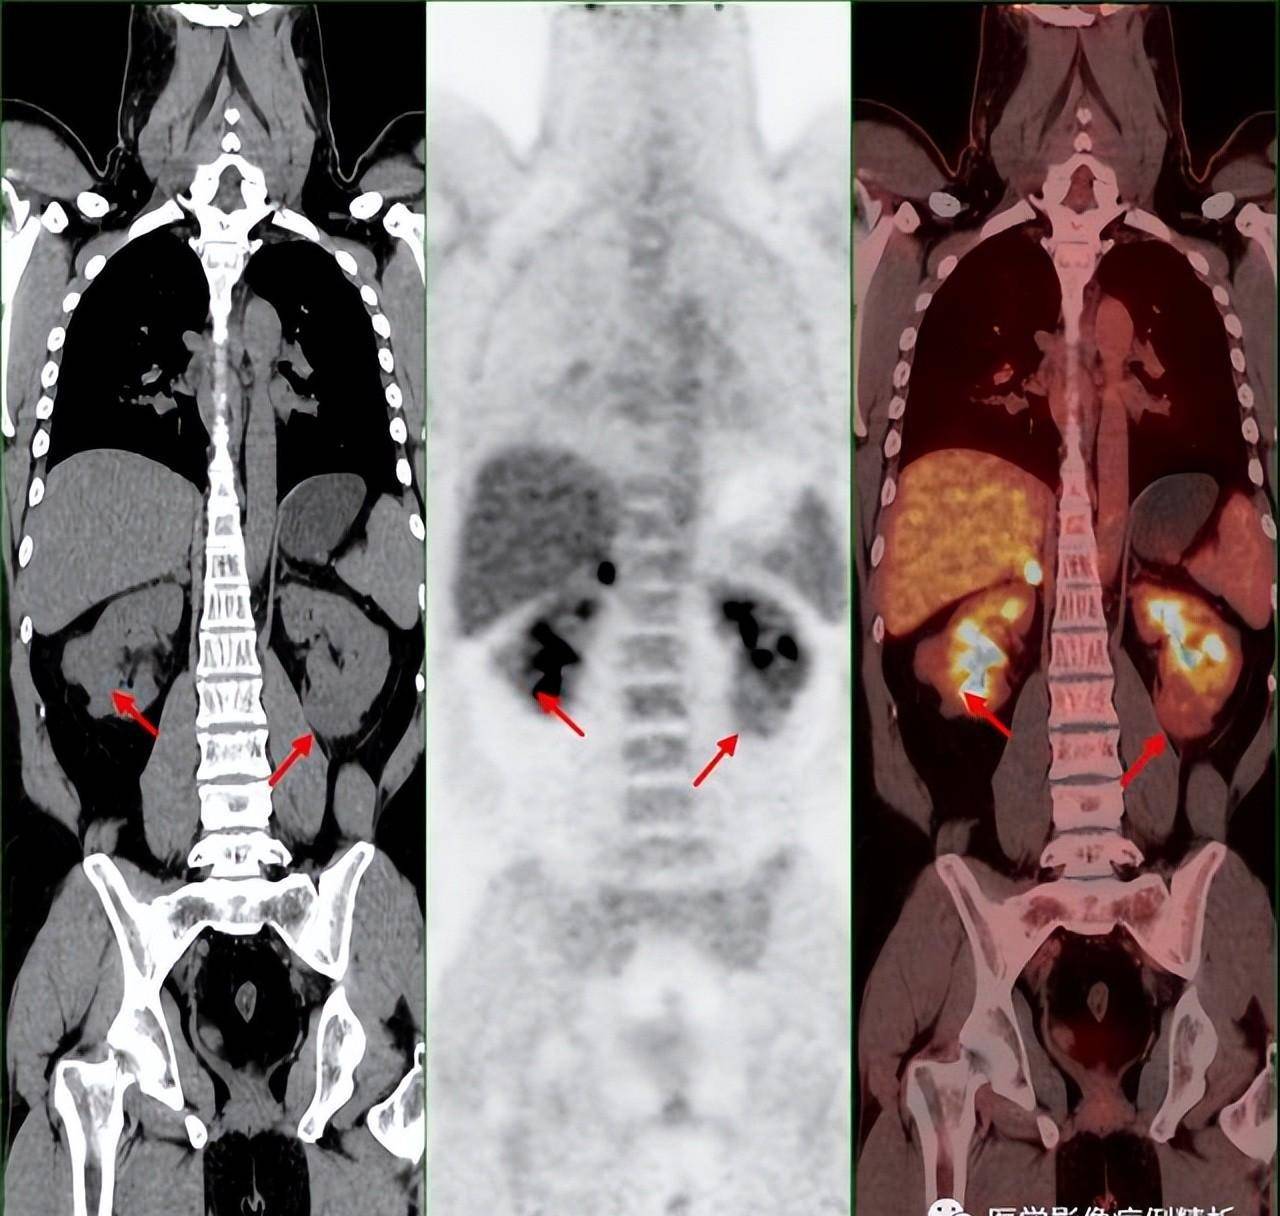

单纯肾病吗?vhl综合征(林岛综合征)pet-ct影像诊断及鉴别诊断